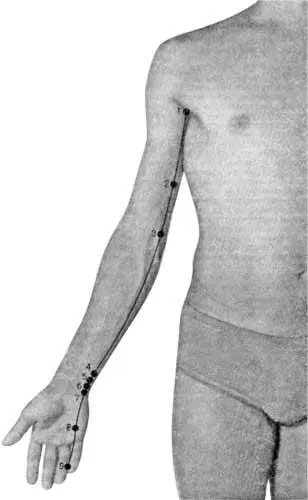

Действительно, язык тесно связан с деятельностью сердца. Царица нашего организма с его помощью выражает свои думы и чаяния. И когда говорят: «Я люблю его (ее) всем сердцем», то это вполне соответствует истине. И наоборот, если ребенок заикается, не может быстро произнести хотя бы пару слов, то это означает, по терминологии китайских целителей, что в меридиане сердца такого пациента поселился «холод» (рис. 32).

Рис. 32. Меридиан сердца (по Г. Лувсан)

1 — цзи-цюань; 2 — цин-лин; 3 — шао-хай; 4 — лин-дао; 5 — тун-ли; 6 — инь-си; 7 — шэнь-мэнь; 8 — шао-фу; 9 — шао-чун

Система инь (+), максимальная активность от 11 до 13 ч, месяц активности — декабрь.

Признаки недостатка энергии: неспособность принимать решения, подавленность, угнетенное состояние, страх, волнение, тревожное состояние. Признаки избытка энергии: те же, что и при недостатке энергии, плюс тяжесть в груди, иногда повышение температуры и сухость во рту.

Показания:боли в области сердца, нарушения сердечного ритма, состояние беспокойства, снижение памяти быстро произнести хотя бы пару слов, то это означает, по терминологии китайских целителей, что в меридиане сердца такого пациента поселился «холод» (рис. 32).